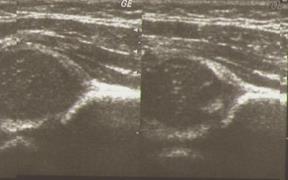

Рис. 5. Сонограмма нормально сформованных тазобедренных суставов.